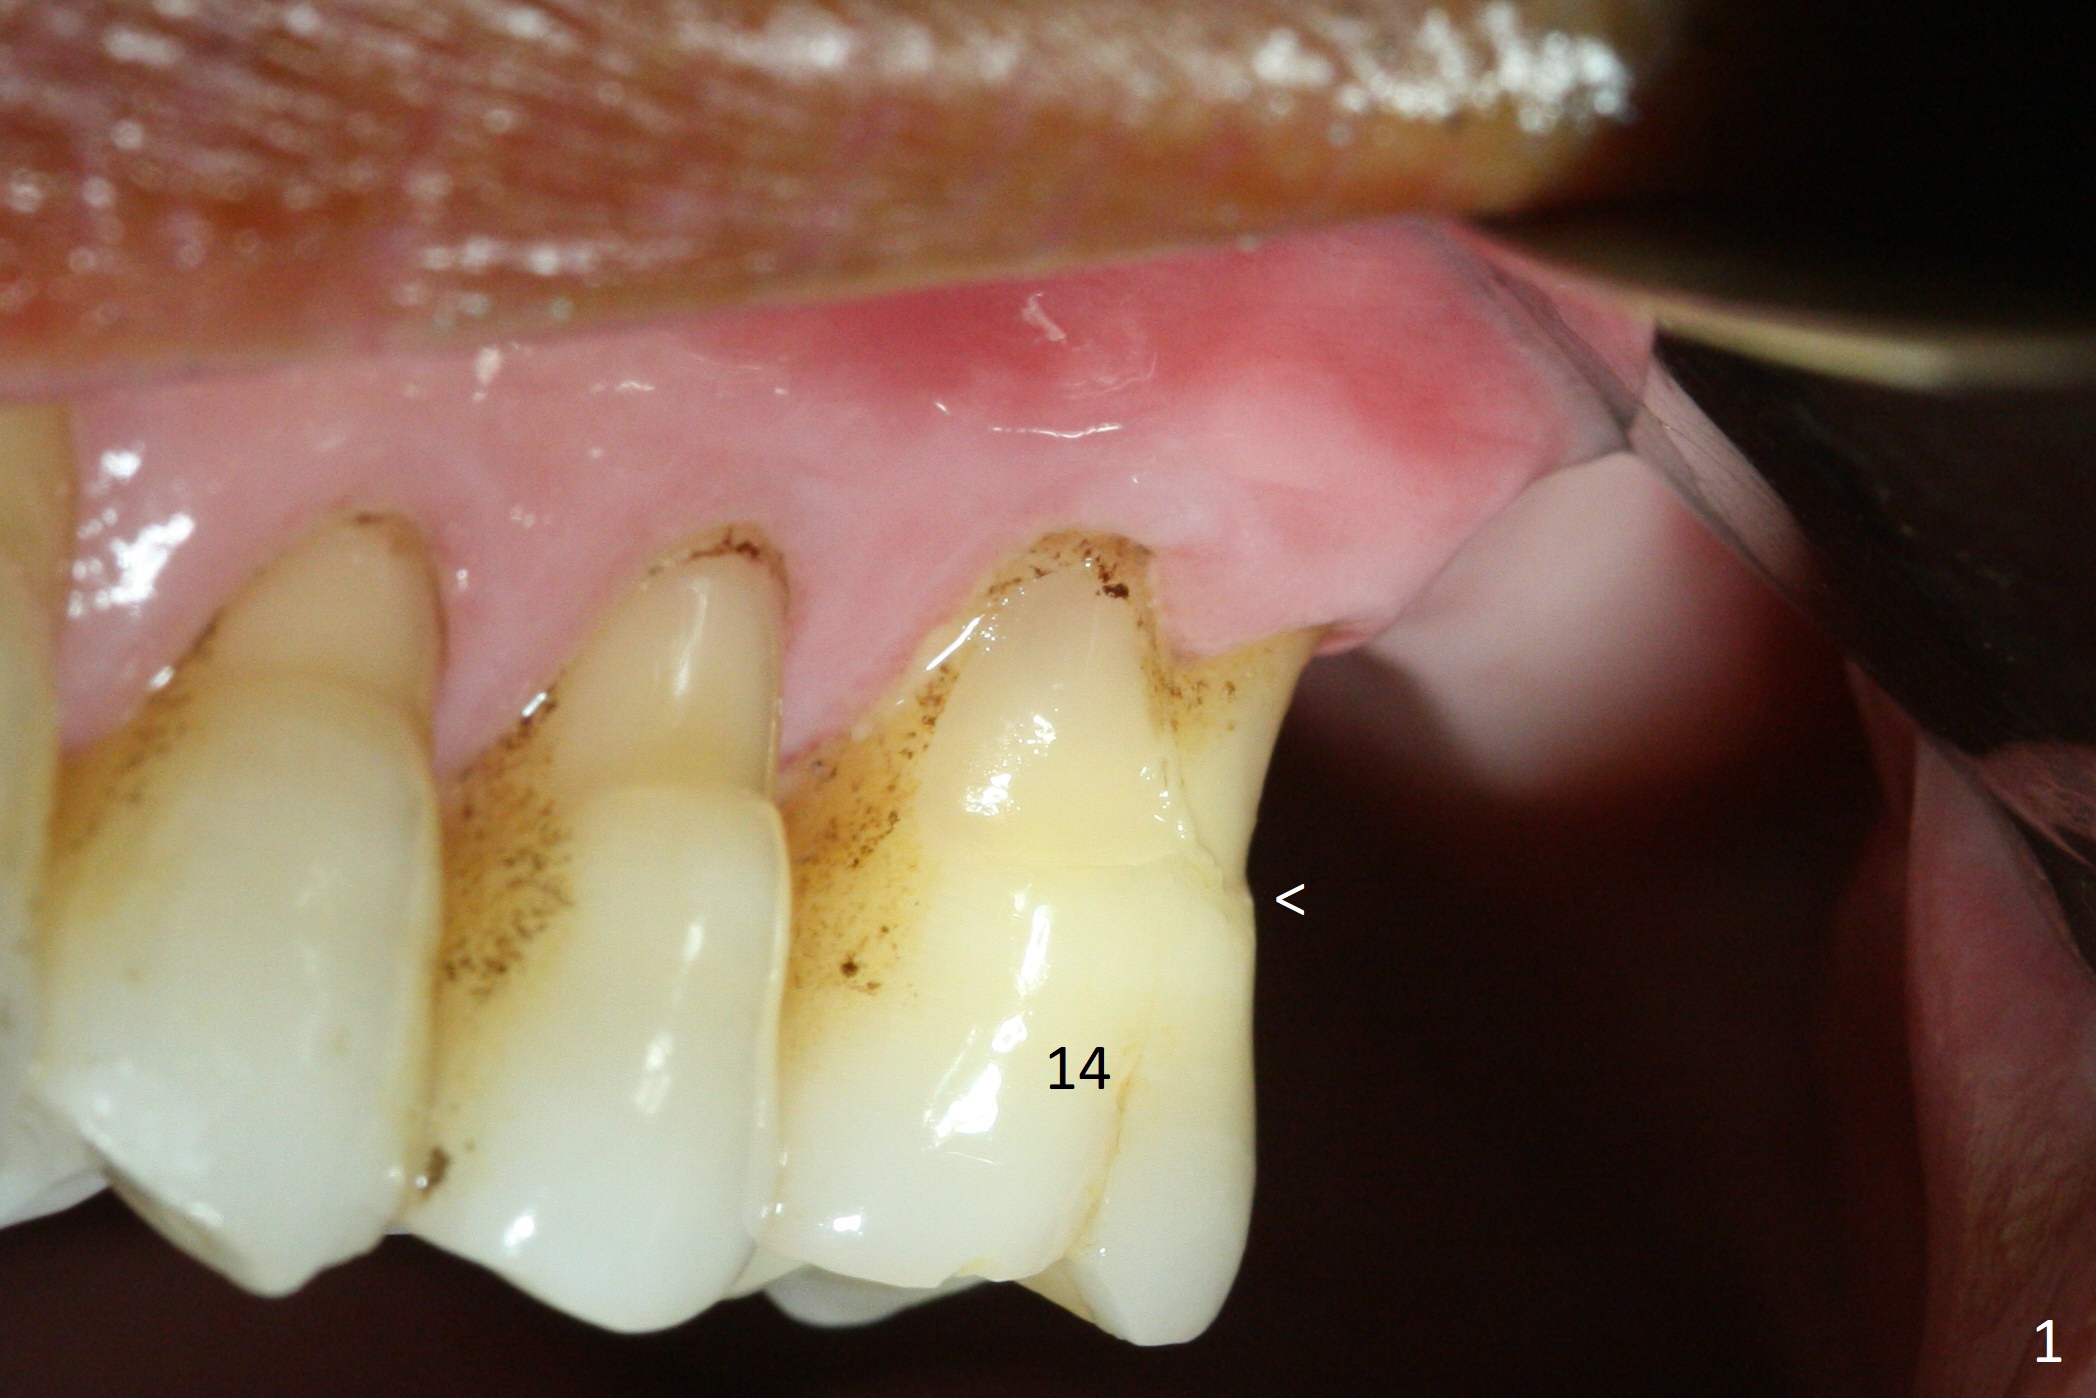

Buccal gingival recession at #14 (Fig.1) is less severe than the palatal one (Fig.2).  Without raising the buccal gingiva (Fig.3 B), osteotomy in the septum is established apparently in the middle socket (Fig.3 *, 4).  As the osteotomy increases with 3.8 mm drill, the palatal wall of the osteotomy starts to be perforating.  When a 4.5x11.5 mm implant is placed, palatal threads are exposed, to which autogenous bone and Vera Graft are placed (Fig.5 *).  After placement of a 5.5x5(3) mm abutment, an immediate provisional (Fig.6 P) is fabricated to cover the sockets.  If the septal dimension were studied carefully by raising the buccal gingiva slightly, the osteotomy could be initially more buccal so that the palatal thread exposure could be less.  When the provisional is removed 1.5 months postop, the implant is exposed palatally.  The margin of the provisional is modified so that the implant can be cleaned by the patient using Water Pik.  In fact, the healthy gingiva seems to be attached to the implant threads 2 weeks later (Fig.7).  The distal implant threads remains exposed 6 months postop; it appears that the distal socket wall has resorbed (Fig.8).  The sockets heal 1 year 7 months post cementation (Fig.9).